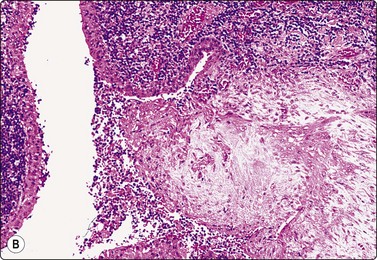

Fig. 4.3 Cystic metastasis of squamous carcinoma

Whole section of cervical lymph node containing metastatic deposit of squamous carcinoma with central cystic degeneration. Note similarity to branchial cyst (HE).

The diagnostic difficulties are due to the fact that squamous epithelial cells aspirated from a cystic metastasis of well-differentiated SCC are often anucleate or of parakeratotic type with a mature cytoplasm and a small pyknotic nucleus appearing cytologically bland, while inflammation of a benign cyst can result in immature squamous metaplasia and worrying cytological atypia. Figures 4.1 and 4.2 compare cells exfoliating from the lining of inflamed branchial cysts with those from cystic SCCs seen in histological sections. Helpful clues are that material sampled from a cystic SCC is more obviously necrotic than inflammatory, and a careful search usually reveals a few squamous epithelial cells with malignant nuclear features or abnormal keratinised cells with bizarre, globoid shapes and dense orangeophilic (Pap) cytoplasm. The nuclear atypia and hyperchromasia seen in squamous cells from a benign cyst is of degenerative type. But the distinction is not always easy (see Figs 4.1C and D). In some cases, the FNB can only be reported as indeterminate. The only ancillary test we have found useful in this setting is HPV DNA sequencing. Occult tonsillar carcinomas and other oral cavity carcinomas with cystic lymph node metastases are a common clinical problem. Many such carcinomas contain HPV DNA as evaluated by PCR or other molecular testing and a positive result in an FNA sample is strong evidence that a lesion is metastatic carcinoma rather than a branchial cleft cyst or other benign cyst.